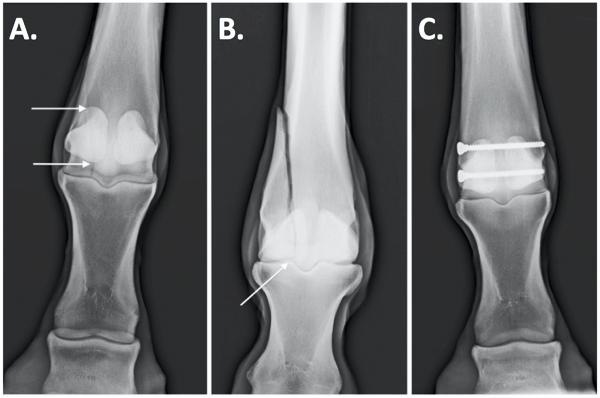

Condylar fractures are the most common long bone fractures in horses. They occur at the bottom of cannon bone where it meets the fetlock joint. They most typically occur in thoroughbred racehorses but are also prevalent in endurance horses and occasionally occur in three-day event horses.